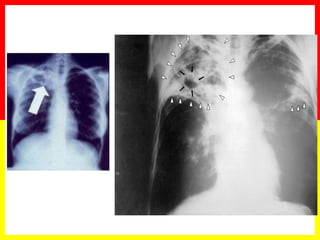

Chest X-rays in diagnosis

No certain x-ray pattern is specific to TB

Radiology

No radiological picture can be characteristic of TB.

CXR can be helpful in localizing abnormalities but not to establish the diagnosis of tuberculosis. Only bacteriology can provide the final proof.

Chest x-rays are necessary in TB suspects who cannot produce sputum or who have negative smears, and where extra-pulmonary TB (such as pleural effusions and pericardial TB) is suspected. They must be interpreted in the light of the patient’s history and other clinical findings.